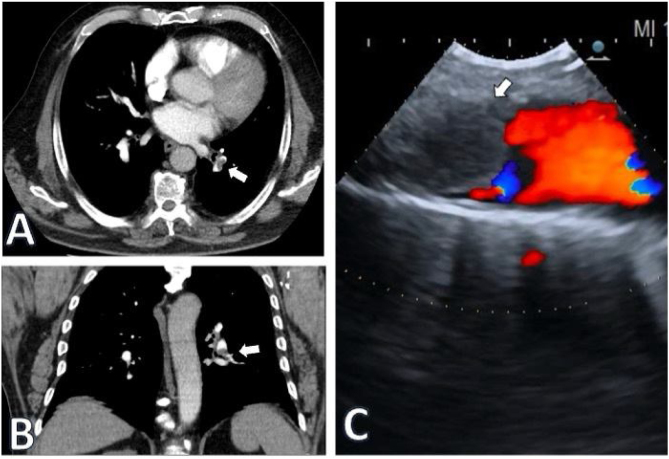

Given this suspicion, the patient was promptly referred to the emergency department for a CT pulmonary angiogram (CTPA), confirming the presence of a left lobar pulmonary embolism (PE), which would justify the dyspnea (Fig. 1).

Fig. 1.

Images of the thrombus in the left pulmonary artery branch, indicated by the arrow, in axial (A) and coronal (B) sections of CTPA. (C) EBUS: Doppler mode image showing the thrombus occluding the arterial circulation.